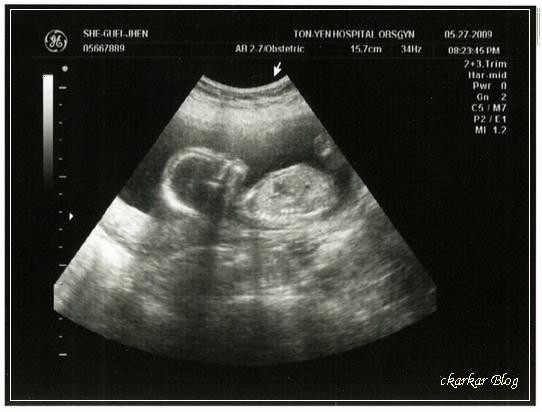

5/27端午節前一天晚上產檢,這一次要自費第二孕期唐氏症篩檢,又要抽血檢查,花了2仟多元,